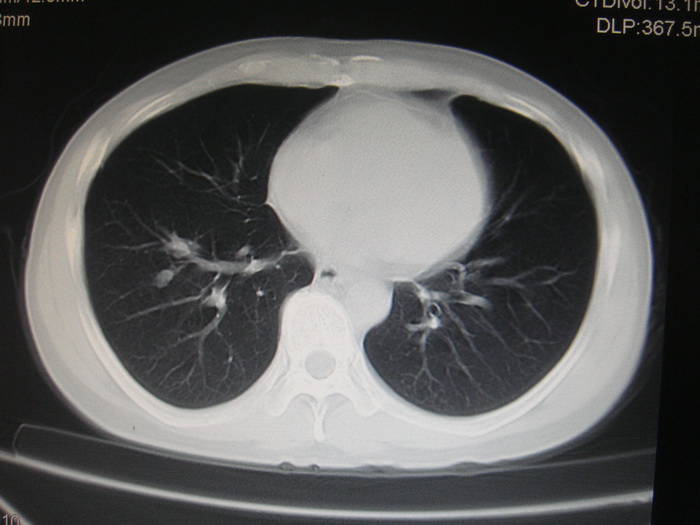

标题: CT28366:男性,45岁,偶尔发现右颈部肿块行胸部CT扫描。 [打印本页]

男性,45岁,偶尔发现右颈部肿块行胸部ct扫描。

两肺多发结节灶及纵膈淋巴结肿大考虑为转移

两肺多发性转移瘤,纵隔淋巴结转移。

两肺多发性转移瘤,纵隔淋巴结转移。食道中上段管壁似乎增厚,作相关检查。

两肺多发性转移瘤,前上纵隔淋巴结转移。